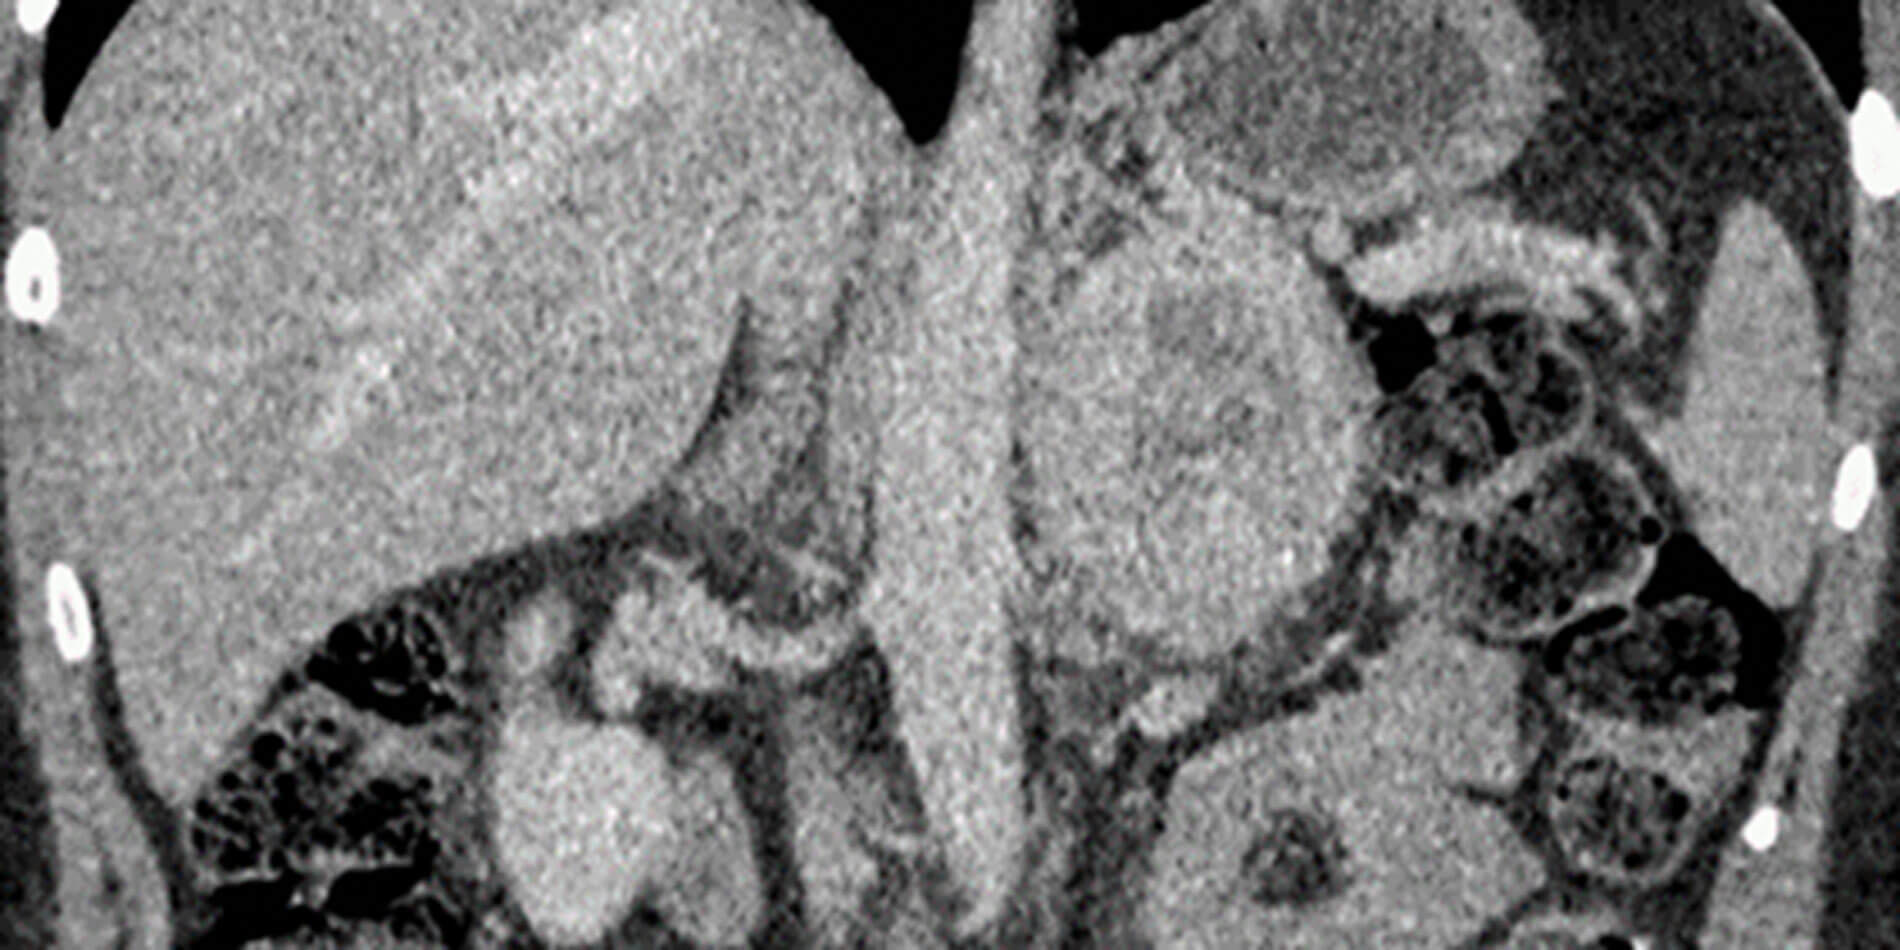

Figure 3: Post contrast coronal CT shows a large mass showing avid enhancement in the peripheral portions and a central non enhancing necrotic area.